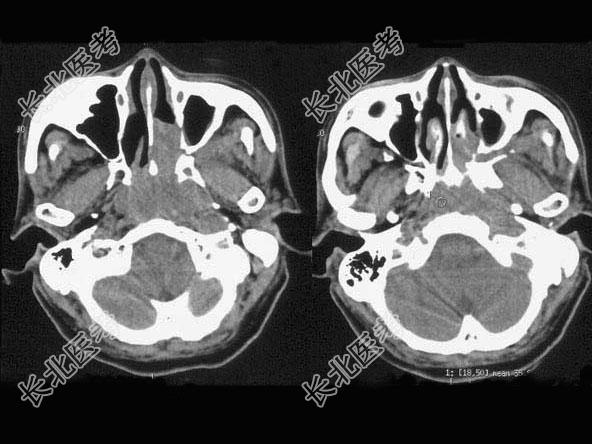

- 单项选择题男,64岁, 间断性流鼻血1年余,近1个月加重, CT如图所示,最可能的诊断是 ( )

E、鼻咽癌